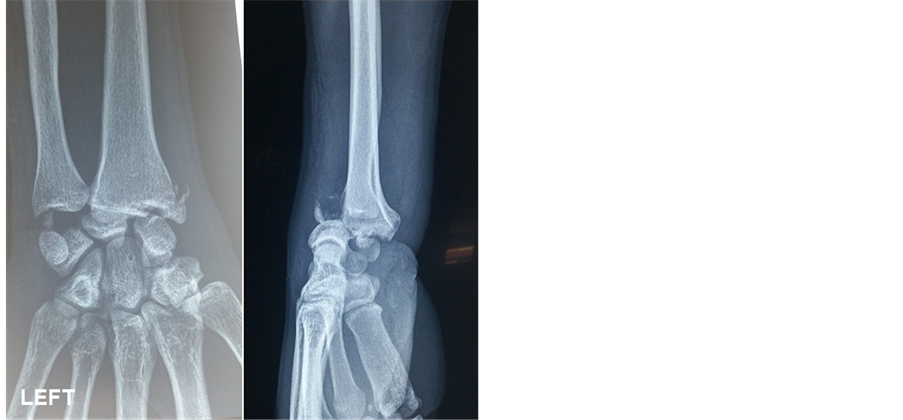

This is a male, 35 year-old patient, builder, without any remarkable medical history who fell from a high place and applied an excessive load to his wrists, which were in extension. He had deformity of both wrists, severe pain and functional disability. Associated to severe pain and functional disability of the right elbow. The initial physical exam found a “dinner fork” deformity in both wrists, increased temperature, severe pain and functional disability. Deformity of the right elbow with ecchymosis. Antero-posterior and lateral wrist X-rays of the wrists and right elbow were taken, which showed dorsal radiocarpal dislocation and fracture of the radial and ulnar styloid process in both wrists (Figure 1 and Figure 2). Dislocation of the right elbow with complex fracture of the radial head and ulnar shaft of the same right upper limb (Figure 3).

Figure 1. Right wrist before treatment.

Figure 2. Left wrist before treatment.